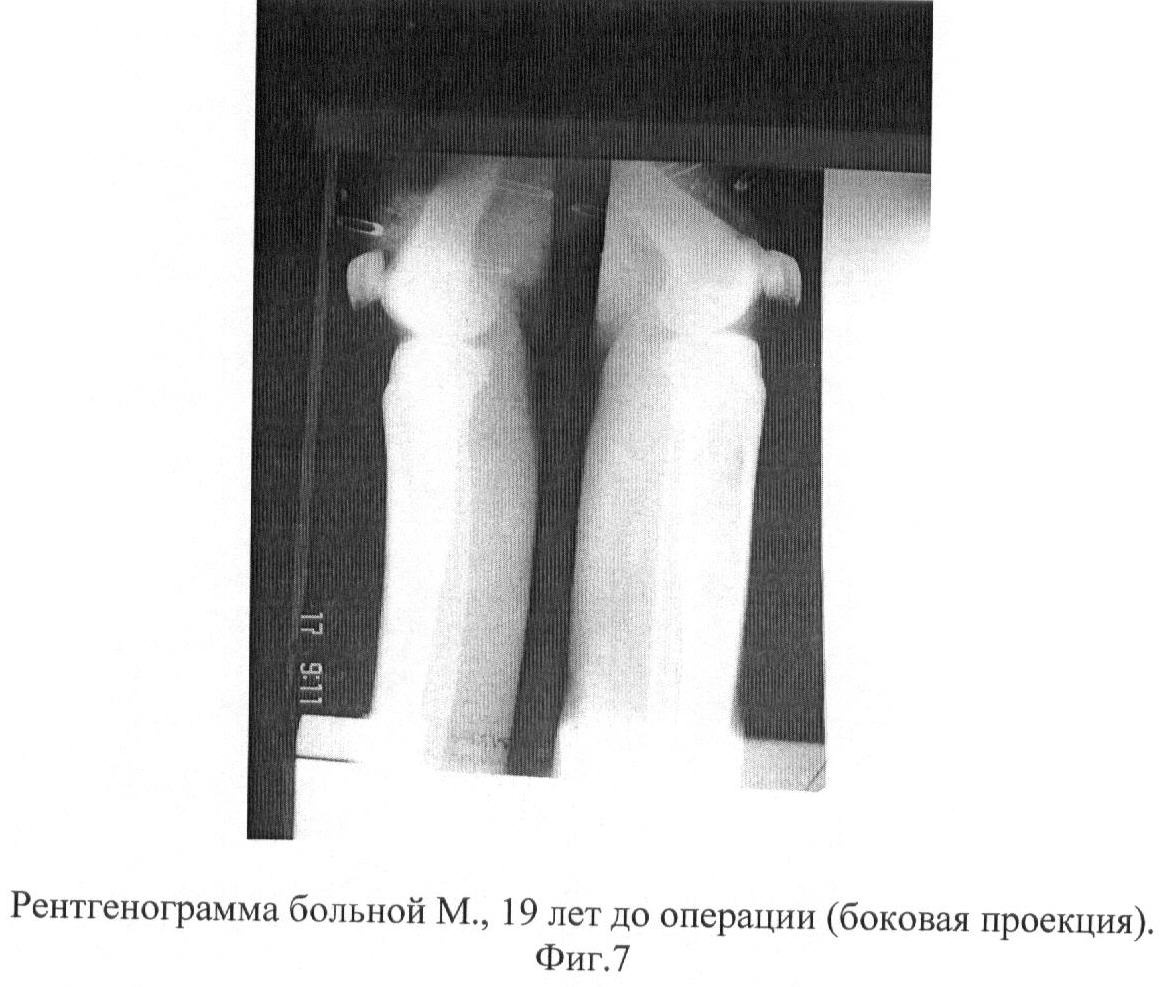

Больная М., 19 лет, обратилась в ГКБ 21 г.Уфы с жалобами на боли в средней трети левой голени. Больной себя считает около 4 лет. В последнее время, перед обращением в клинику ГКБ 21 появились усиливающиеся боли после нагрузок, варусная деформация левой голени.

Больной проведено обследование: компьютерная томография обеих голеней, рентгенография, операционная биопсия костной ткани и полости кисты (цитологическое, гистологическое и бактериологическое исследование костной ткани). Данные гистологического, цитологического исследования: атипичные клетки не выявлены. Роста микрофлоры при бактериологическом посеве не обнаружено. Имеется опасность патологического перелома в зоне очага аневризмальной кисты, так как толщина кортикального слоя костной ткани составляет 1-2 мм. (фиг.5-7).

На клиническом разборе решено провести оперативное лечение: краевая резекция большеберцовой кости, интрамедуллярный блокирующий остеосинтез с костной пластикой дефекта аллоплантом. Решение провести блокирующий остеосинтез было вызвано тем, что имелась опасность перелома из-за потери механической прочности кости после ее краевой резекции, а длительная внешняя иммобилизация и длительная ходьба на костылях вела к тяжелым последствиям (контрактуры суставов, синдром Зудека и пр.). После соответствующей подготовки больная была прооперирована по вышеописанной методике (фиг.8).